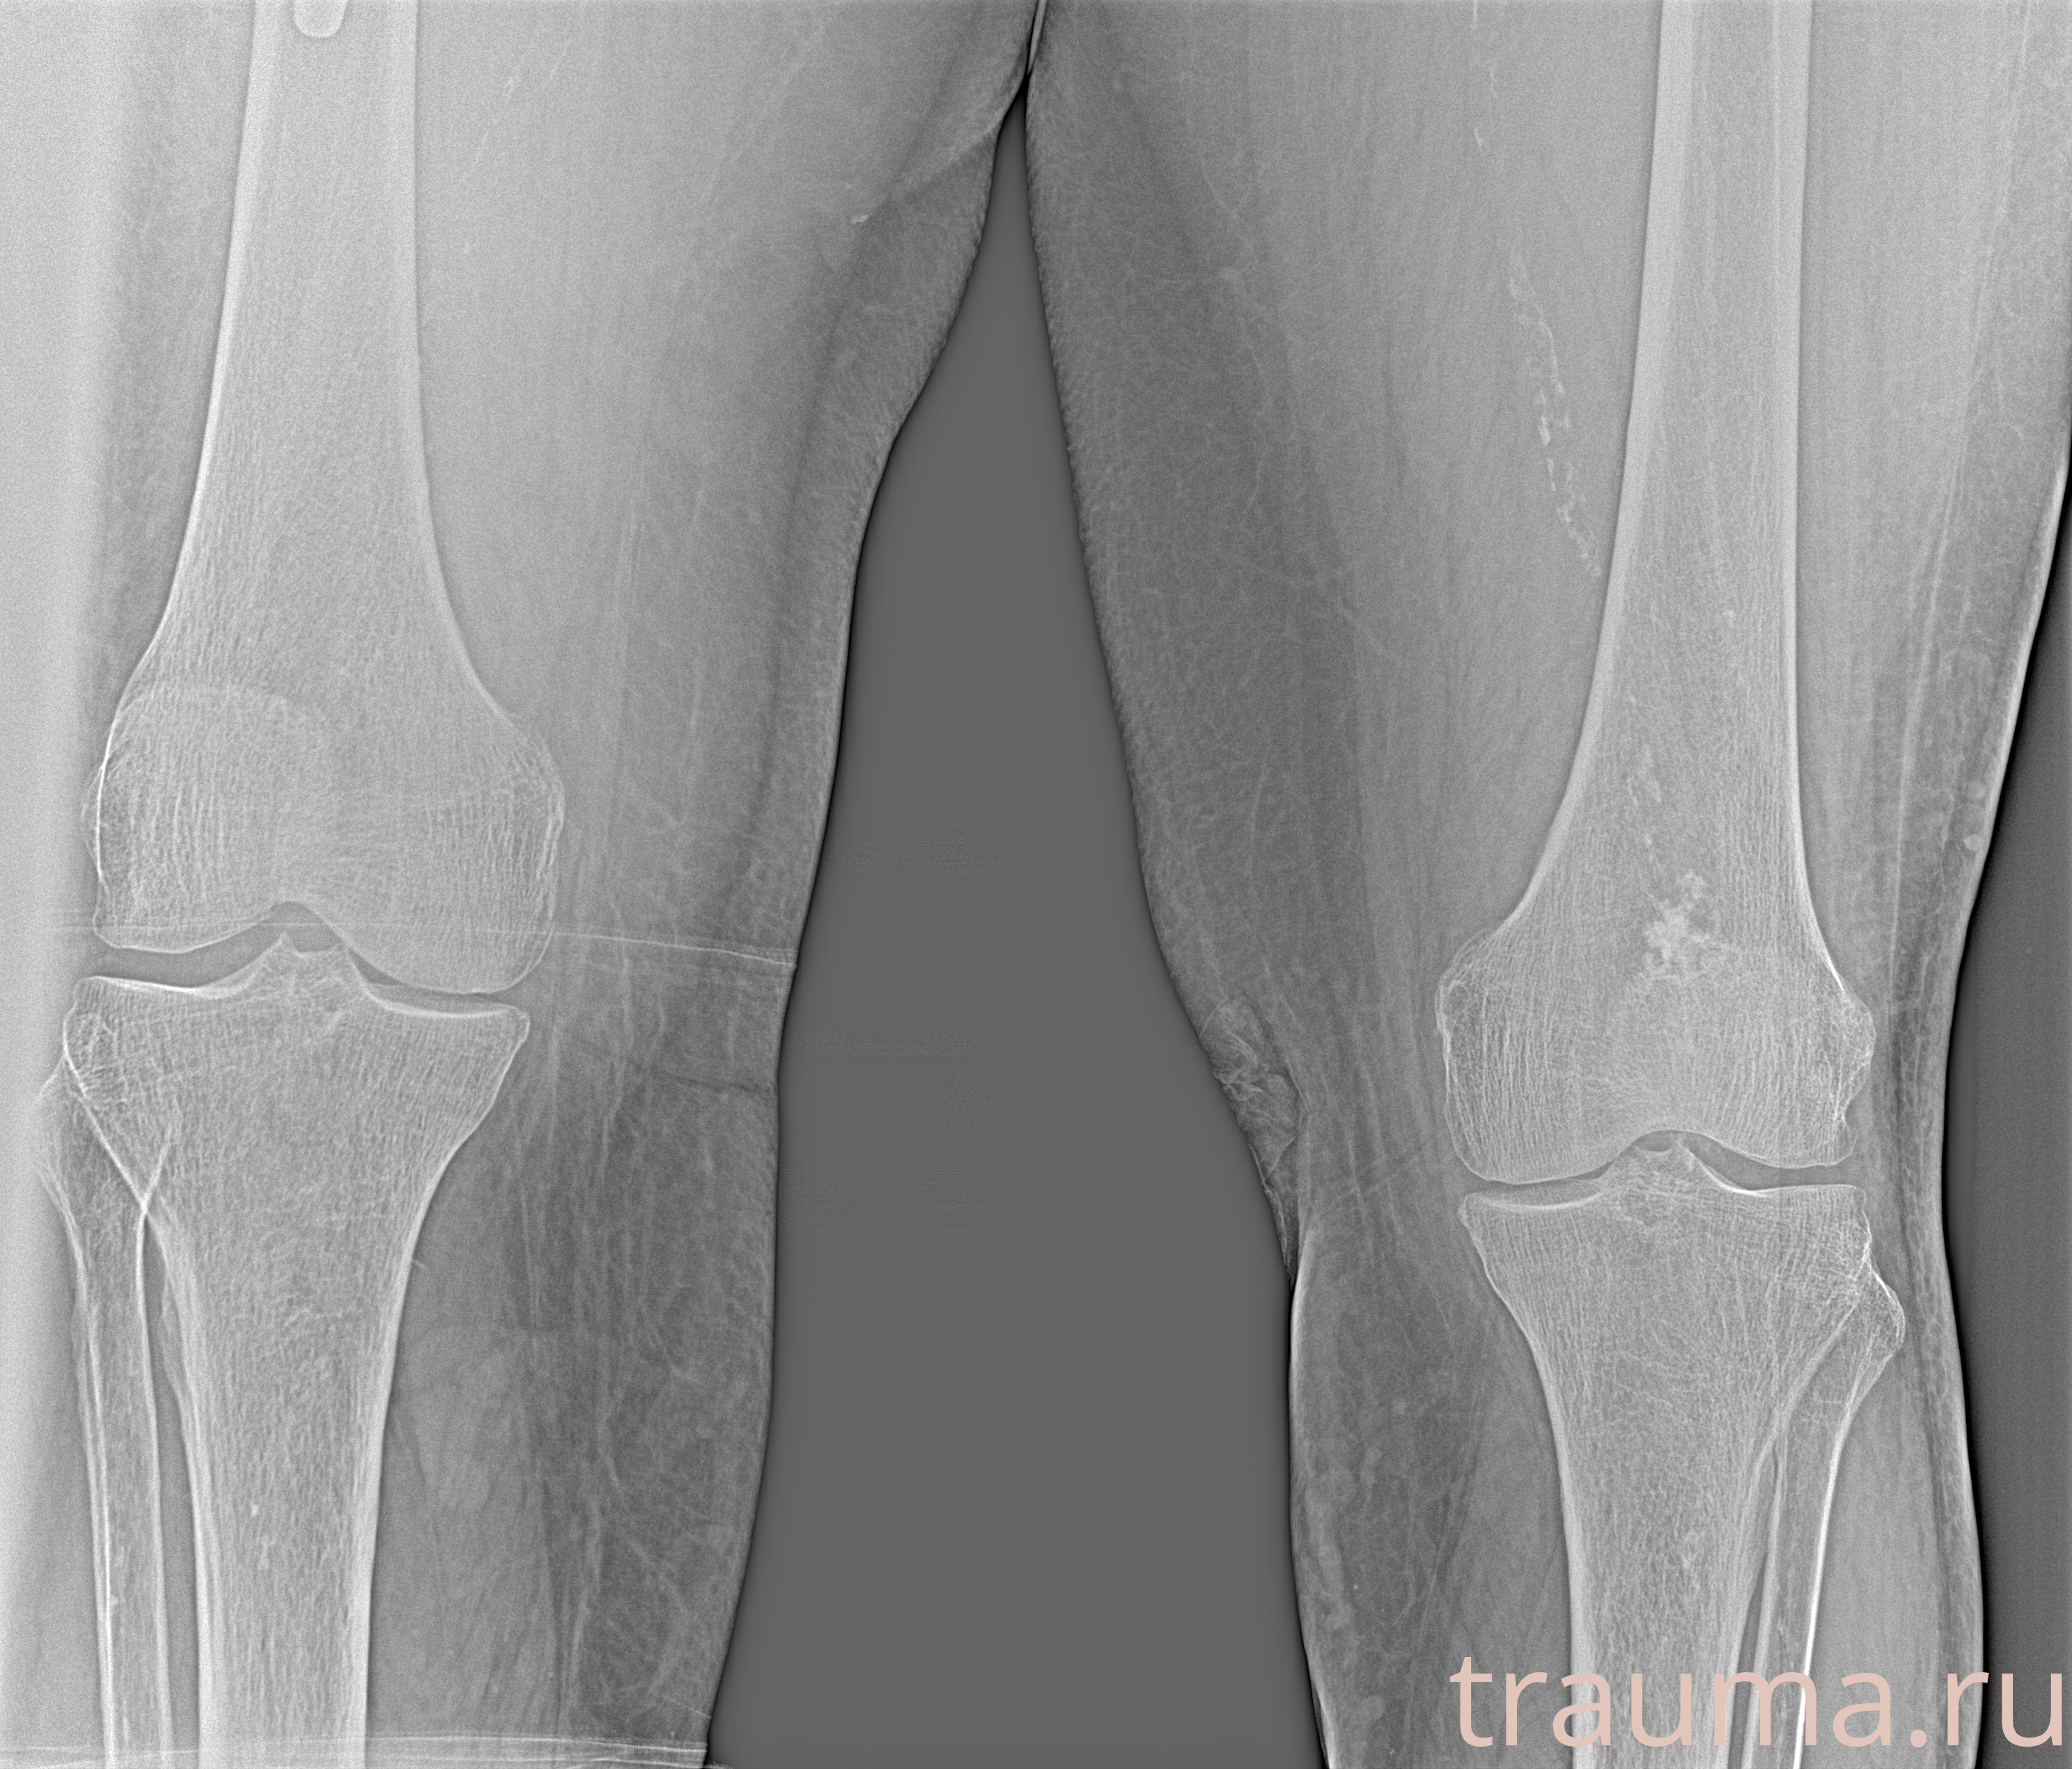

Рентгенограммы